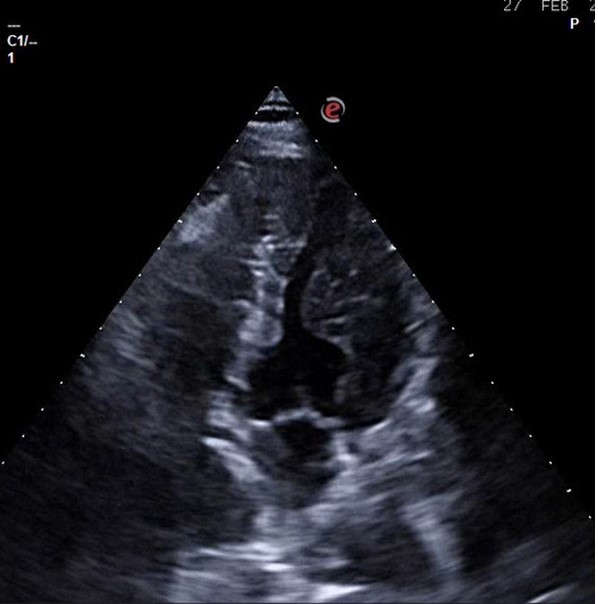

En nuestro centro se le realizó Ecocardioscopia: En eje paraesternal largo se observa grosor parietal aumentado más a nivel septal y de predominio en septo basal donde alcanza los 18 mm. VI no dilatado. FEVI conservada. No alteración de la contractilidad ni valvulopatías.